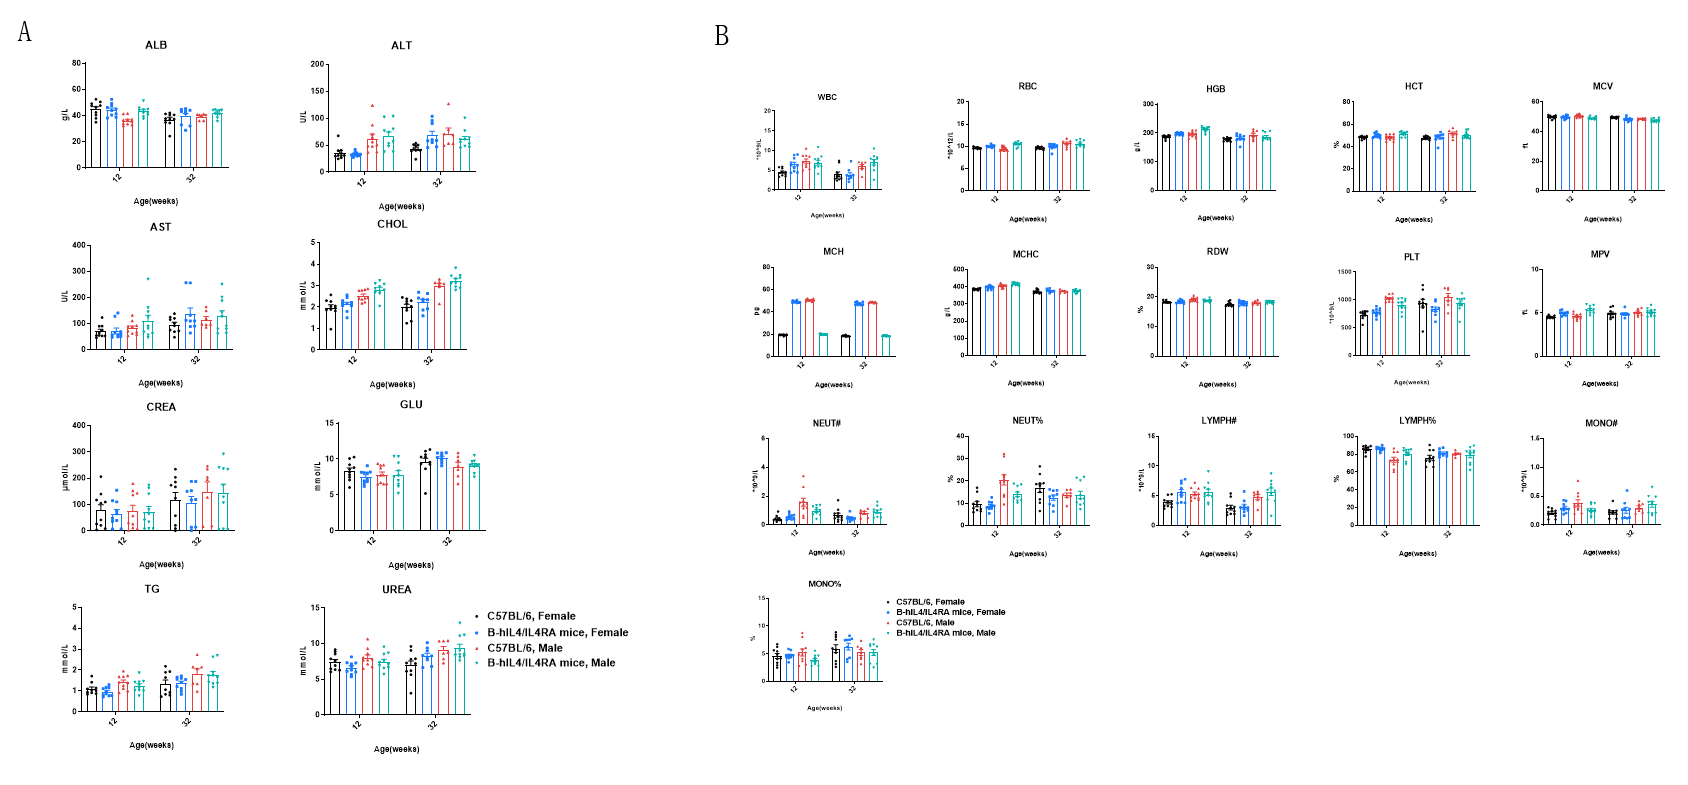

Blood biochemistry and hematology analysis of wild-type mice and B-hIL4/hIL4RA mice measured at 12 and 32 weeks of age. 12-week-old wild-type C57BL/6 mice and B-hIL4/hIL4RA mice (10 males and 10 females) were monitored for 32 weeks to assess overall health of the animals. (A) Biochemistry analysis. (B) Hematology analysis. The data showed that biochemistry analysis and hematology analysis were also similar between B-hIL4/hIL4RA humanized mice and wild-type C57BL/6 mice.